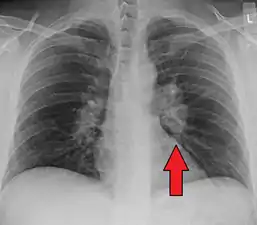

Chest radiograph changes are divided into four stages:[105]

- bihilar lymphadenopathy

- bihilar lymphadenopathy and reticulonodular infiltrates

- bilateral pulmonary infiltrates

- fibrocystic sarcoidosis typically with upward hilar retraction, cystic and bullous changes

Although people with stage 1 radiographs tend to have the acute or subacute, reversible form of the disease, those with stages 2 and 3 often have the chronic, progressive disease; these patterns do not represent consecutive "stages" of sarcoidosis. Thus, except for epidemiologic purposes, this categorization is mostly of historic interest.[28]

Hilar adenopathy especially on the person's left (AP CXR)

Hilar adenopathy especially on the person's left (lateral CXR)